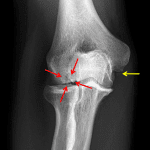

Indication: Elbow pain

Findings

- No acute fracture or malalignment

- Osteochondral lesion of the capitellum measuring 10 x 6 mm

- Remote ununited avulsion fracture at the site of humeral attachment of the ulnar collateral ligament

Diagnosis

- Osteochondral lesion of the capitellum

No acute fracture or malalignment.

No elbow joint effusion.

Osteochondral lesion of the capitellum measuring 10 x 6 mm. No evidence of intraarticular body. Consider MRI to assess for signs of instability.

Remote ununited avulsion fracture at the site of humeral attachment of the ulnar collateral ligament.